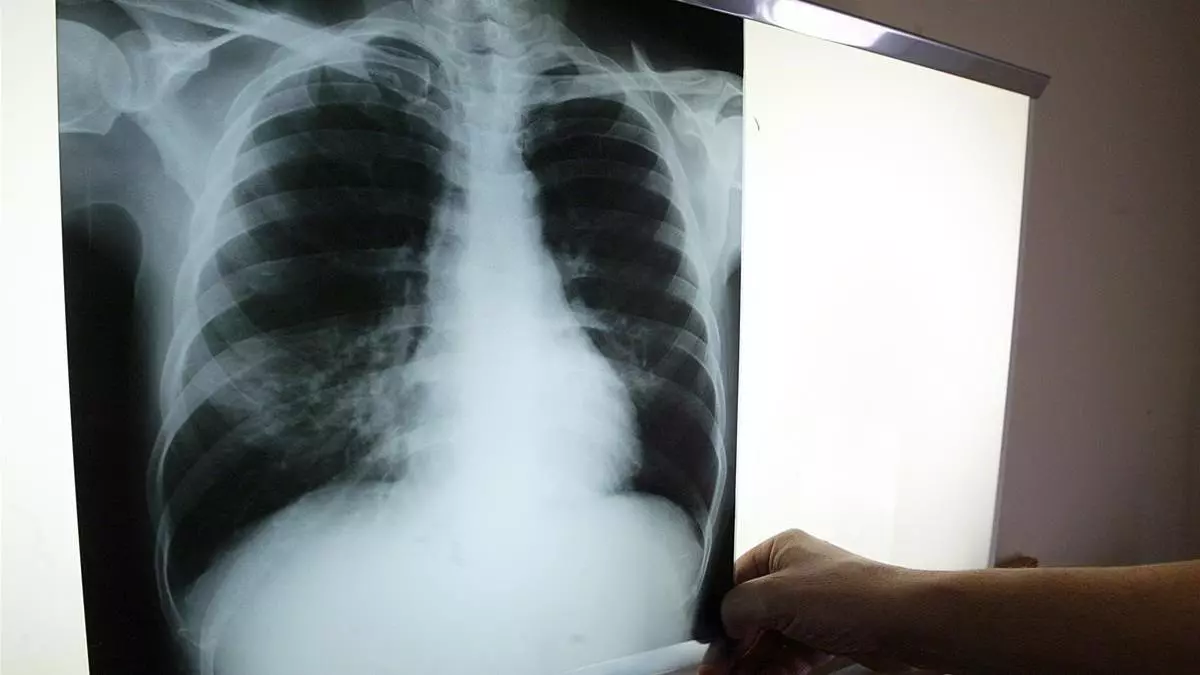

En Catalunya hubo un total de 1.001 casos de tuberculosis en el 2017, el último año del que la Agència de Salut Pública de Catalunya (Aspcat) dispone de datos. La tasa disminuyó en un 0,8% con respecto de la del año anterior. Esta infección bacteriana, que se transmite a través del aire y que suele atacar los pulmones, se reduce lentamente cada año en Catalunya, pero sin embargo no logra erradicarse, entre otros motivos porque sigue siendo la cuarta causa de mortalidad en un mundo cada vez más global, con cada vez más movimientos de personas.

La tuberculosis puede atacar a los pulmones, a los riñones, a la columna vertebral y al cerebro. La tuberculosis pulmonar, que es la más frecuente tiene como síntomas una tos de más de tres semanas de duración que no se cura ni con antibióticos, pérdida de peso e incluso fiebre. Catalunya cuenta con el centro Serveis Clínics, concertado con el Servei Català de la Salut (CatSalut), que atiende a los pacientes con tuberculosis cuando estos no pueden seguir el tratamiento en su domicilio.